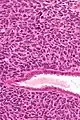

| Micrograph of a uterine adenosarcoma showing a mitotically active malignant stroma and benign glands. H&E stain. | |

Uterine adenosarcoma is an uncommon form of cancer that arises from mesenchymal tissue of the uterus and has a benign glandular component.

Uterine adenosarcoma have, by definition, a malignant stroma and benign glandular elements. The World Health Organization (WHO) criteria have a mitotic rate cut point; however, this is often disregarded, as bland-appearing tumours with a low mitotic rate are known to metastasize occasionally.[2]